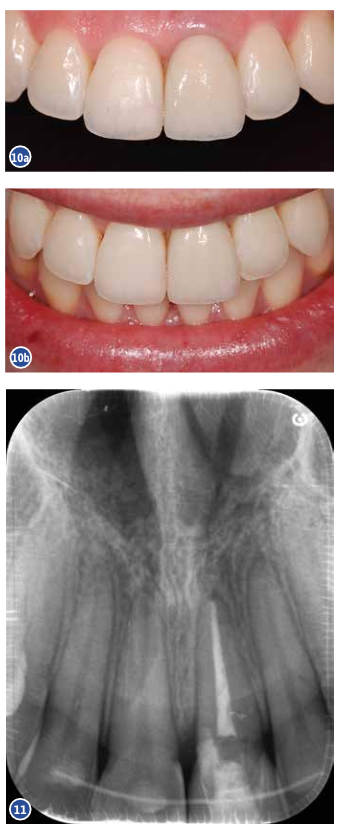

Kontrollvisiidi ajaks oli mesiaalne kontakt taastunud. Kliiniliselt on näha head laminaadi

integratsiooni (fotod 10a ja 10b). Samal visiidil tehti ka kontrollülesvõte (foto 11).